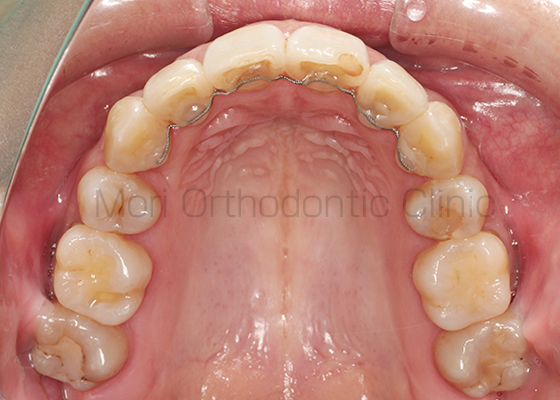

術前